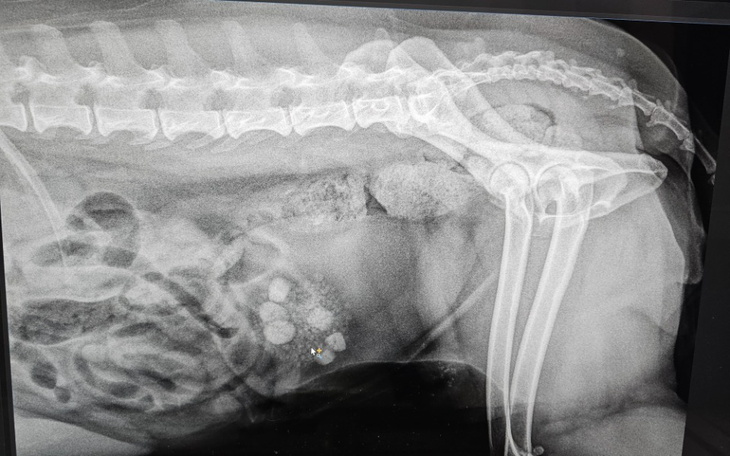

Przeprowadzając się do domu na wieś zauważyliśmy błąkającego się po wsi psa, okazało się, że ma na imię Pusia i poprzedni mieszkańcy zostawili ją tutaj na pastwę losu i żyła jedynie dzięki mieszkańcom wsi, którzy ją dokarmiali. Pusia zaczęła przychodzić też do nas i również zaczęliśmy ją dokarmiać, jednak potrwało to kilka dni, a pewnego dnia Pusia nie zjawiła się, poszłam jej więc poszukać i znalazłam ją skuloną leżącą w krzakach, natychmiast zabrałam ją do weterynarza gdzie zrobiono USG, RTG i inne potrzebne badania i okazało się że Pusia ma w sobie gnijące rozkładające się trzy szczeniaki, których z powodu ich wielkości prawdopodobnie nie mogła urodzić, by ratować jej życie potrzebny był niemal natychmiastowy zabieg, wzięliśmy ją do domu, a już na drugi dzień rano zawieźliśmy na operację, podczas kilkugodzinnej operacji oczekiwaliśmy na wieści od weterynarza, gdy zadzwonił okazało się, że Pusia dwa razy podczas operacji "odeszła" i trzeba było ją reanimować, podczas drugiej takiej sytuacji mieli jej już nie reanimować, bo uważali że może to i tak nie pomóc, jednak zdecydowali się dać jej szansę (ogromnie za to dziękujemy❤️) i Pusię udało się uratować, spędziła noc w lecznicy, noc która miała być decydująca dla niej.. Na drugi dzień otrzymaliśmy informację, że żyje, ale jest bardzo słaba, mimo to jednak możemy zabrać ją do domu. Po operacji musieliśmy podłączać jej kroplówki w domu, próbować karmić, ale niestety praktycznie nic nie jadła, nie była w stanie ustać na nogach długi czas, gdy po około 2 tygodniach zaczęła chodzić po domu okazało się że z zaszytej rany coś się sączy, natychmiast zadzwoniliśmy do weterynarza, który mimo niedzieli wieczór kazał nam przyjechać i stwierdził, że potrzebna jest natychmiast druga operacja bo wdało się zakażenie. Kolejny więc raz czekaliśmy na skończenie operacji, Pusi został wycięty większy kawałek zakażonej skóry, została ponownie zaszyta, a jej skóra była bardzo naciągnięta bo zwyczajnie już jej brakowało, mogliśmy zabrać ją do domu. Tak mijały kolejne tygodnie podawania kroplówek, zastrzyków, leków oraz próby karmienia Pusi. Gdy doszła już do siebie, a rana była niemal zagojona okazało się, że po wyjściu na dwór na dłuższą chwilę ma ona bardzo duże zaburzenia równowagi i chwieje nią na boki jakby miała się przewrócić. Weterynarz zbadała ją pod kątem neurologicznym, ale nie było żadnych nieprawidłowości, zostało stwierdzone że prawdopodobnie dzieje się tak z powodu bardzo dużego osłabienia organizmu i faktycznie po kilku miesiącach minęło. Zaczęło się jednak obsesyjne drapanie do krwi i gryzienie, zostały zrobione przez nas testy na alergię i okazało się, że Pusia uczulona jest na groch, ryż i kukurydzę, więc została zmieniona całkowicie jej dieta, po tym objawy ustały, tylko czasem przy pyleniu jakichś drzew zdarzają się sporadyczne krótkie drapania jednak nie wpływają one na jej samopoczucie ani życie. Pusia jest już z nami ponad 5 lat, przeżyła z nami nie jedną podróż i jest traktowana jak członek rodziny, dotychczas wszystko z jej zdrowiem było już w porządku, jednak ostatnio wieczorem zaczęła biegać po domu i piszczeć, nie wiedzieliśmy co się dzieje, poszliśmy z nią na spacer i okazało się że podczas spaceru próbowała około 25 razy się wysikać, ale nie mogła, wróciliśmy do domu i mimo, że nie załatwia się nigdy w domu to co chwilę próbowała się w domu wysikać, również bezskutecznie. Nie mogłam dodzwonić się do naszego weterynarza, więc podałam jej leki na pęcherz oraz rozkurczające (tak, wiedziałam jakie i w jakiej dawce) i na zmianę całą noc siedzieliśmy z nią czekając do rana by jechać do naszego zaufanego weterynarza, całe szczęście po lekach udało jej się zasnąć i spokojnie spała do rana bez większych pobudek, a rano udało jej się już załatwić. U weterynarza zostało zrobione od razu USG i RTG, okazało się że Pusia ma w pęcherzu drobniejsze kamienie oraz większe osiągające 1cm, ponadto ma też guza listwy mlecznej, który stwierdzono już wcześniej, ale prawdopodobnie okazuje się że zaczyna on rosnąć więc jest do usunięcia wraz z biopsją, kamienie również są do usunięcia jak najszybciej, jeden z nich prawdopodobnie przytkał cewkę moczową i spowodował wyżej wymienione objawy, leki które podałam spowodowały najprawdopodobniej cofnięcie się kamienia, ale nadal bardzo drażnią one pęcherz a w najgorszym przypadku może wystąpić tam podobno rak płaskonabłonkowy, nie chcemy do tego dopuścić, dodatkowo jej zęby są w okropnym stanie, kilka przednich samo wypadło, co do reszty wskazane jest usunięcie i oczyszczenie z kamienia tego co zostanie, jest to również ważne ponieważ problemy z zębami mogą powodować problemy z wątrobą i innymi narządami. Dotychczas opłacaliśmy wszystkie operacje, zabiegi i leczenia z własnej kieszeni mimo że były to ogromne kwoty, oraz zawsze staraliśmy się wspierać wszystkie zbiórki i akcje w którym można pomoc zwierzętom, jednak teraz potrzebujemy Twojej pomocy, nie możemy dopuścić żeby Pusia męczyła się w oczekiwaniu na operację i ryzykować jej życiem. Obecnie Pusia jest na antybiotykach oraz lekach na pęcherz, do czasu zabiegu mieliśmy też podawać specjalną karmę ale niestety okazało się, że ma w składzie wszystko to na co Pusia jest uczulona, więc tymbardziej musimy się pospieszyć. Dziękujemy za każdą pomoc ❤️